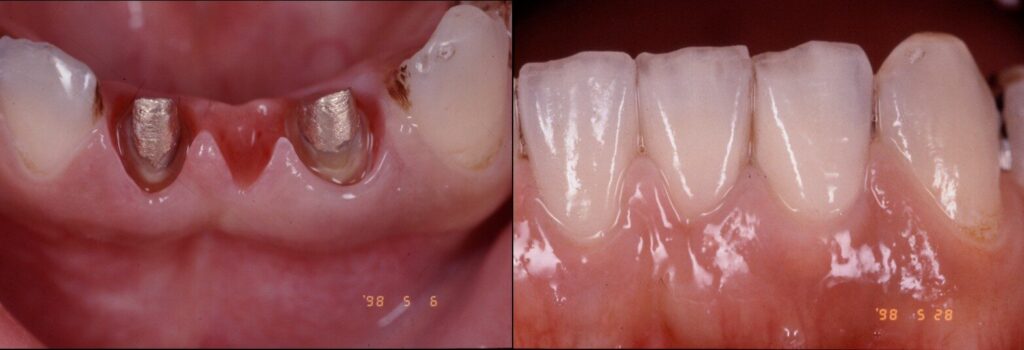

臨床例